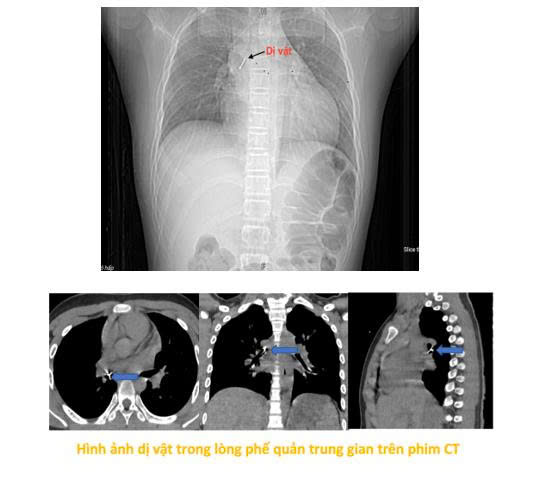

Tại đây, qua chụp cắt lớp vi tính lồng ngực và nội soi phế quản, các bác sĩ phát hiện dị vật kim loại sắc nhọn đã mắc sâu trong phế quản trung gian bên phải, đâm xuyên thành phế quản gây chảy máu và phù nề niêm mạc. Do vị trí nguy hiểm và dị vật sắc nhọn, thủ thuật gắp gặp rất nhiều khó khăn. Sau hơn hai giờ nỗ lực không thành công, bệnh nhi được chuyển khẩn cấp sang Bệnh viện Phổi Trung ương.

Tiếp nhận ca bệnh, ThS.BSCKII Nguyễn Lê Nhật Minh – Trưởng khoa Nội soi chẩn đoán và can thiệp cùng ê-kíp đã nhanh chóng tiến hành thủ thuật nội soi phế quản ống mềm để xử trí. "Dị vật là chiếc đinh ghim sắc nhọn, đầu nhọn đâm xuyên sâu vào thành phế quản.

Đây là ca gắp dị vật rất khó vì chỉ cần thao tác lệch hoặc chậm có thể khiến đinh ghim rơi xuống sâu hơn, gây rách phế quản, tràn khí màng phổi hoặc suy hô hấp cấp"- bác sĩ Minh chia sẻ.